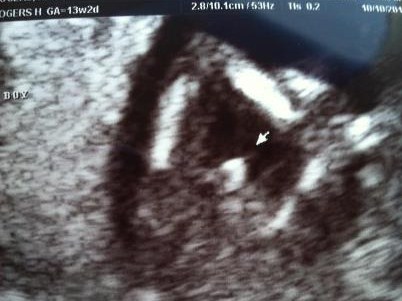

Attachment 5285Have full sonogram session but here is a potti shot of him.Attachment 5284

I was 13 wks 2 days in this photo. Sorry I had forgot to answer that question for you.